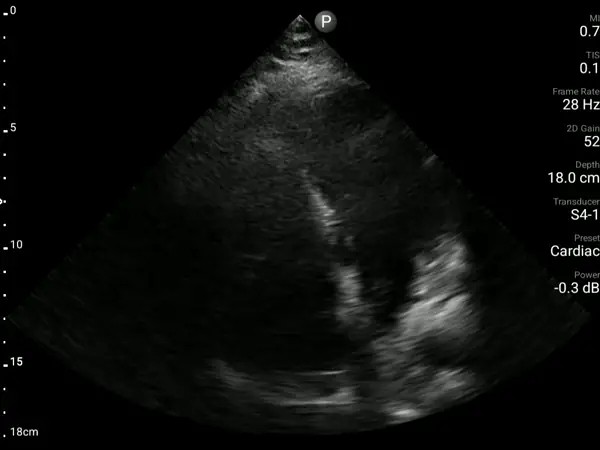

A 47-year-old woman with obesity, hypertension, dyslipidemia, and a history of chronic heart failure presented with shortness of breath, peripheral edema, and clinical signs of deterioration. Without on-site echocardiography, her worsening status could not be objectively assessed. A bedside AISAP exam revealed EF 14%, severe mitral regurgitation, and severe tricuspid regurgitation, confirming significant decline from her prior evaluation. In this low-resource setting, AISAP provided the essential diagnostic clarity needed to guide timely management during an acute heart failure exacerbation.